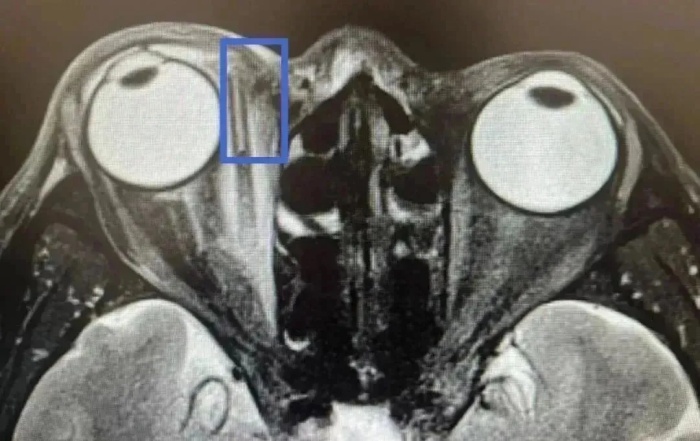

詳細詢問受傷過程時,王老伯始終否認有異物進入眼里。但眼眶磁共振檢查顯示,王老伯右眼深處內支肌旁有一長條異物。

當天,張宗端主任立即為王老伯施行眶內異物取出+清創(chuàng)縫合術,術中取出如筷子粗,長約3厘米的樹枝。